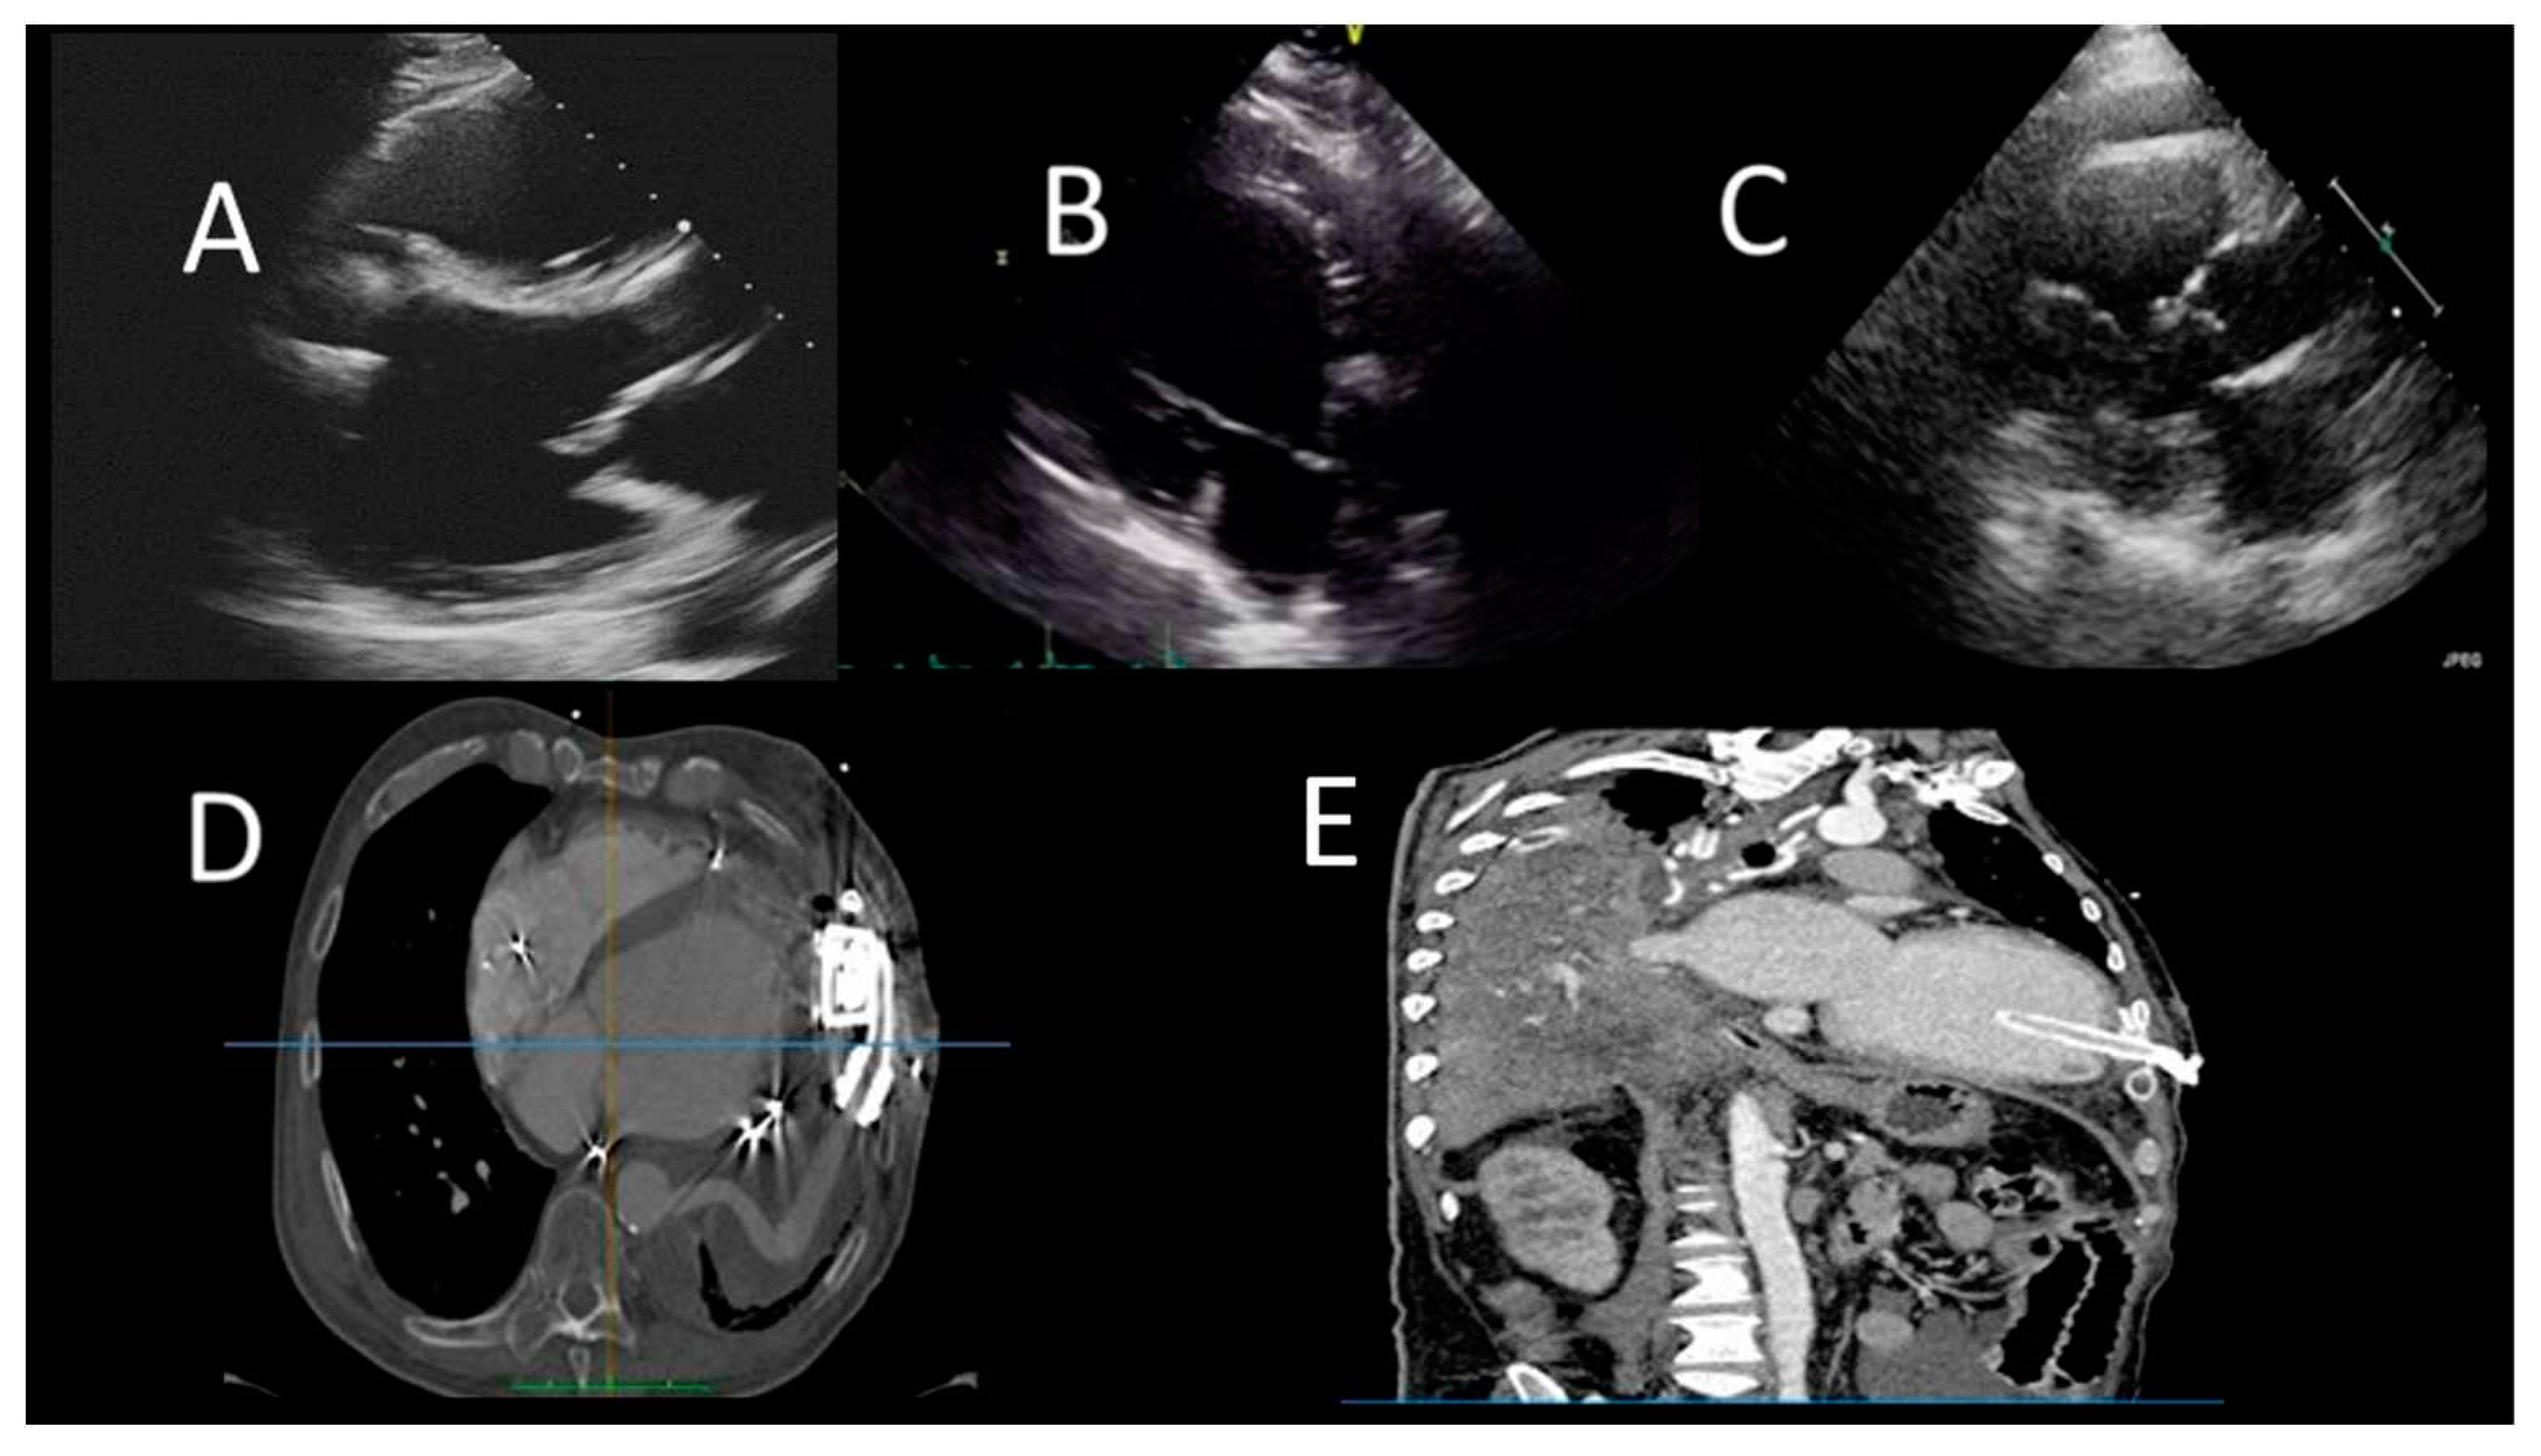

Figure 4. Evaluation after LVAD assist device. A) TTE evaluation (PLAX) shows normal position of IVS and the inflow cannula; B) TTE (PLAX) of LVAD patient, showing incorrect right-convex position of the IVS; C) TTE evaluation (PLAX) of LVAD patient, showing incorrect left-convex position of the IVS; D) CCT showing hematoma around LV cannula; E) CCT showing small LV apical thrombus.

Figure 6. Evaluation of cardiac plaques in OTC patients by CCT. A) mild LAD circumferential soft plaque; B) occlusion of LCx artery; C) mild RCA soft plaque; D) Increased pFAI values suggestive of coronary artery inflammation.

2.4.3. Cardiac Magnetic Resonance

CMR allows an early identification of rejection and CAV in OCT patients (52-54). Moreover, the presence of late gadolinium enhancement was found to be prognostically relevant, although its sensitive is low in OCT patients (53). The new mapping techniques may have an emerging role in the diagnosis of OCT rejection (54). T1-mapping showed to decrease after successful treatment and to display excellent negative predictive value for the non-invasive detection of rejection (52). Using a multiparametric sequential approach by combining T2 mapping with extracellular volume fraction (ECV), diagnostic accuracy of CMR for detecting ACR improves (53) (Figure 5). Finally, stress perfusion CMR can be useful in assessing the microvascular disease through the estimation of myocardial perfusion reserve (MPR) which has a high sensitivity in detecting CAV (54).

2.4.3. Cardiac computed tomography angiography

CCT has increasingly been used to detect CAV in OTC patients (55-57). Wever-Pinzon et al. in a meta-analysis of 13 studies evaluated 615 HTx patients, demonstrating a high diagnostic specificity, sensibility, and accuracy of CCT in comparison with invasive coronary angiography (ICA) for the detection of any CAV and significant CAV using 16 and 64-slice CCT (55). In addition, CAC<0 was associated with an increased risk of MACE, death, graft loss and showed a good correlation with International Society for Heart and Lung Transplantation (ISHLT) CAV grade (58).

Newer CCT technologies, such as dual source CT and multidetector CT, increasing temporal and spatial resolution, allow a better acquisition even at higher rate as in the denervated transplanted heart (55-57). More recently, Nous et al. in a prospective observational study on 129 OTC patients demonstrated that CCT (using 2° and 3° generation dual source CT) could be a safe and accurate alternative to ICA in CAV evaluation (Figure 6).

Interestingly, in small retrospective studies, quantitative coronary wall assessment and plaque analysis allowed an early detection of CAV not detected by ICA (57). Finally, Budde et al. demonstrated that 25% of OTC patients with a focal stenosis >30% showed low value of FFR-CT; even without a focal stenosis, FFR-CT values were found often abnormal in Htx patients (59). Table 6 describes the timing and role of different imaging modalities in OCT.